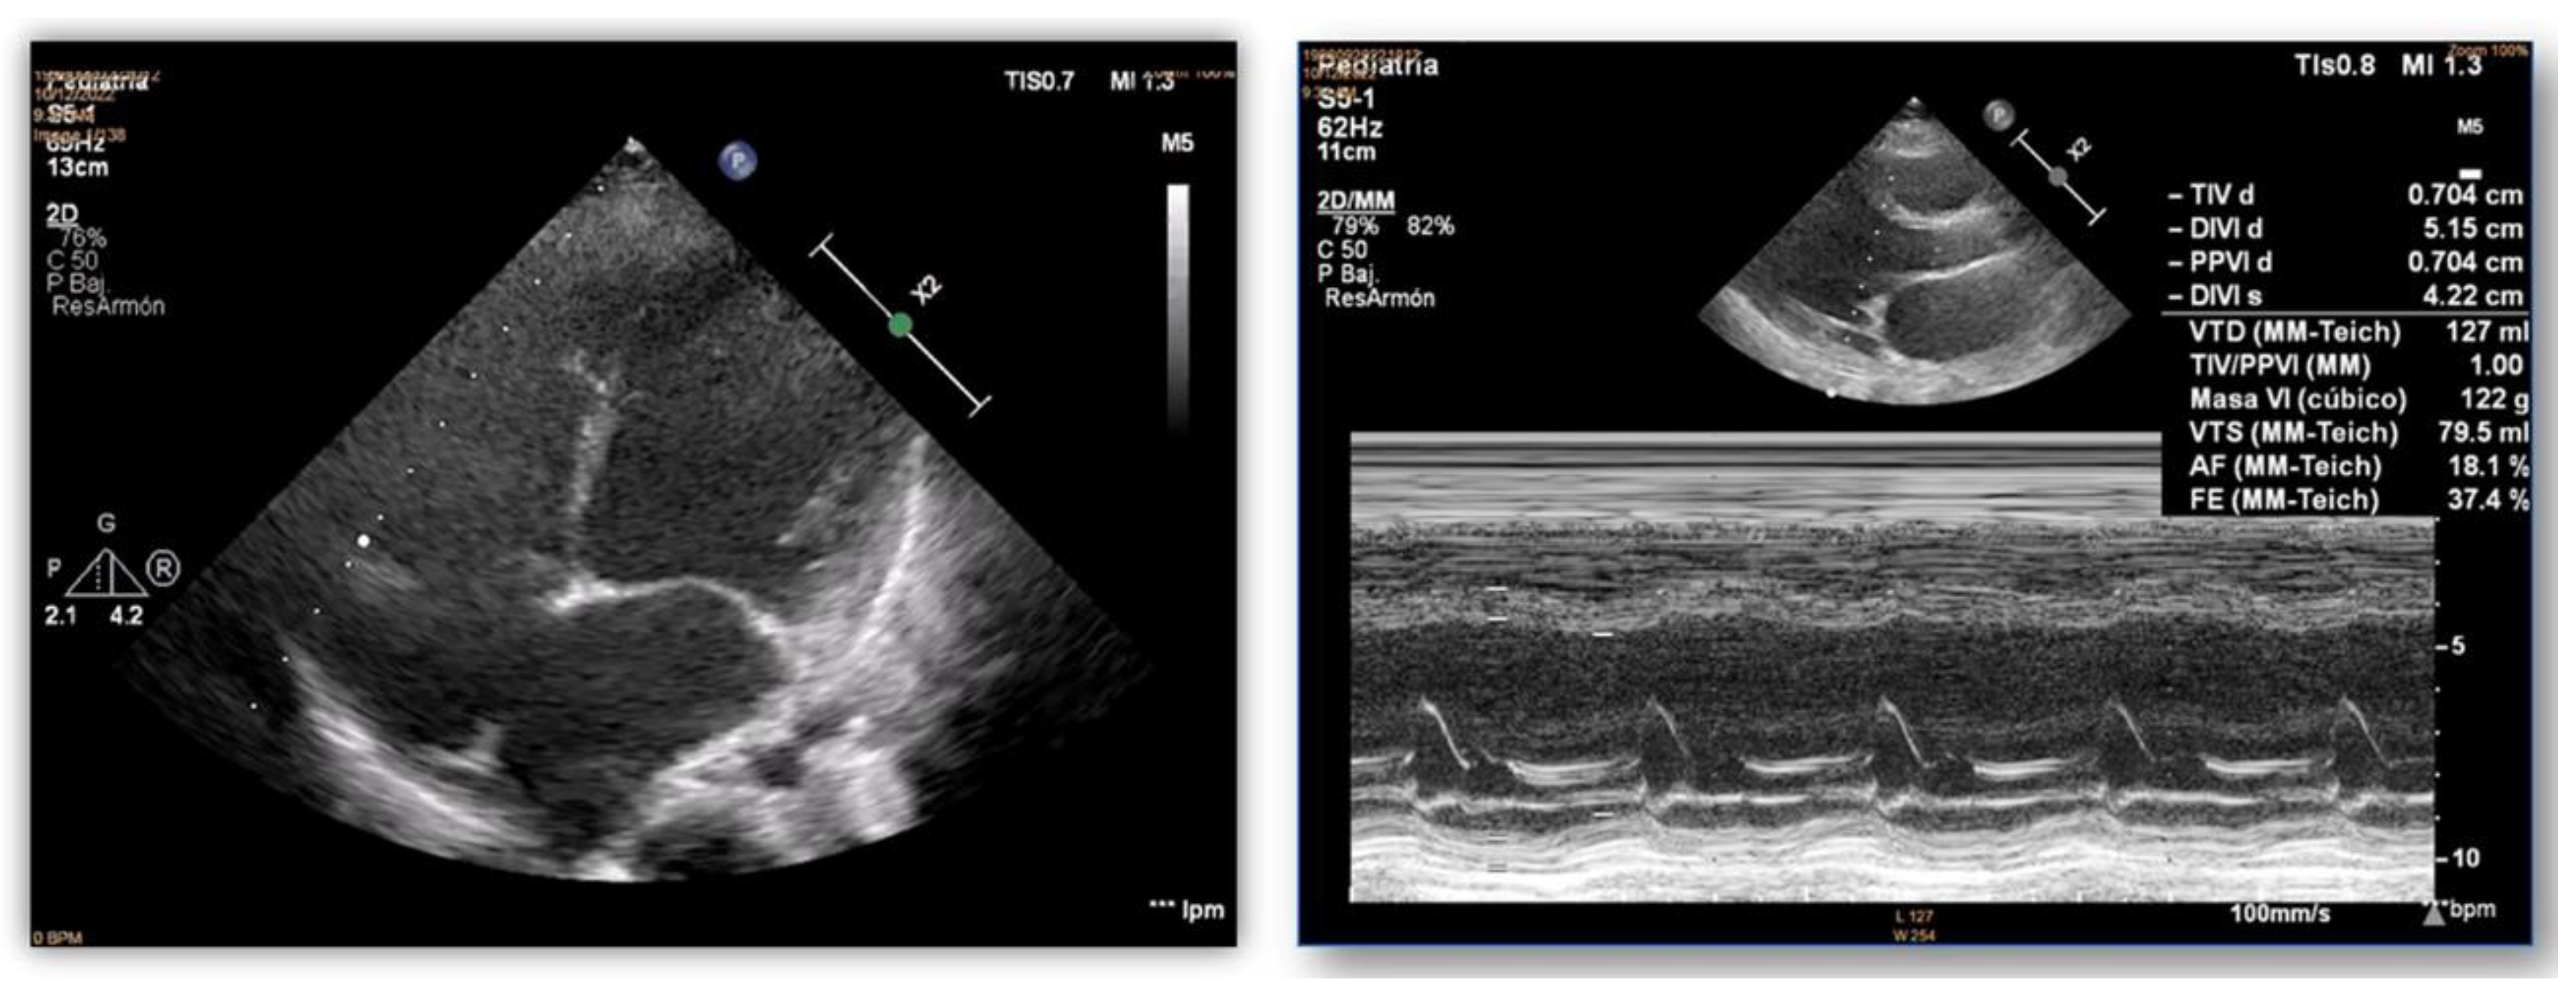

2. Results

2.1. Clinical Data